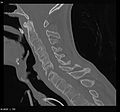

"Bamboo spine" develops when the outer fibers of the fibrous ring (anulus fibrosus disci intervertebralis) of the intervertebral discs ossify, which results in the formation of marginal syndesmophytes between adjoining vertebrae.

The earliest changes demonstrable by plain X-ray shows erosions and sclerosis in sacroiliac joints. Progression of the erosions leads to widening of the joint space and bony sclerosis. X-ray spine can reveal squaring of vertebrae with bony spur formation called syndesmophyte. This causes the bamboo spine appearance. A drawback of X-ray diagnosis is the signs and symptoms of AS have usually been established as long as 7–10 years prior to X-ray-evident changes occurring on a plain film X-ray, which means a delay of as long as 10 years before adequate therapies can be introduced.[25]

CT scan showing bamboo spine in ankylosing spondylitis